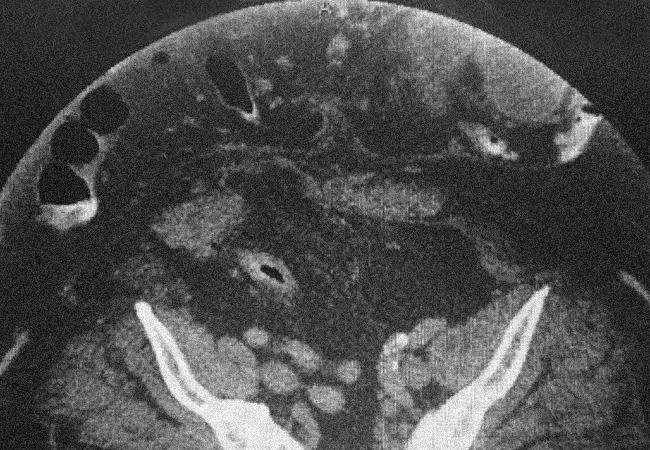

Saggital view of CT scan demonstrates more visceral content outside of the abdominal cavity than inside the abdominal cavity.